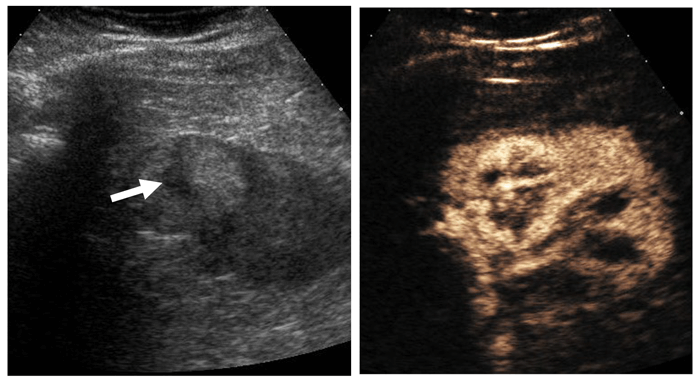

Papillary RCC is often hypointense on T2-weighted sequences and demonstrates low-level homogenous contrast enhancement (Figure 10). Clear cell RCC on the other hand appears hyperintense on T2-weighted sequences with intense heterogenous contrast enhancement and early wash-out.

Figure 10: Type I papillary RCC demonstrating quite low-level homogenous enhancement (left).

Bosniak IV cystic lesion within the contralateral kidney (right) also excised revealing papillary RCC.